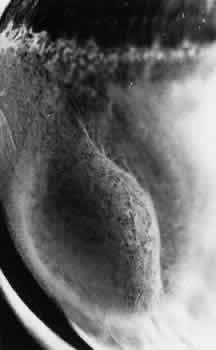

DEGENERATIVE RETINOSCHISIS

Degenerative retinoschisis, a more extensive trophic process, presents as a round or ovoid area of retinal splitting with a smooth fusiform elevation of the inner layer (Fig. 17). The schisis is surrounded on all sides by typical cystoid degeneration; the retinal pillars of the cystoid degeneration as well as the broken pillars near the margin of the schists are prominent. Vessels are located in the inner retinal layer, the intraretinal cavity is optically empty, and the outer retinal layer is moderately irregular in contour.13,14

Fig. 17. Typical degenerative retinoschisis.Note extensive region of typical cystoid degeneration with a rounded and elevated posterior margin. In the center (arrow), radial columns are randomly disrupted, causing a disturbance in coarse surface pattern. (× 18.)